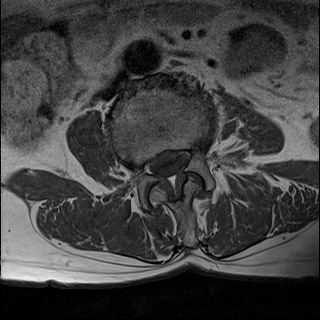

Ӵϲ ɿ ô ô 㸮 ٸ ̾ϴ. ϵ Ͻð ܻ 㸮 20⵿ ͽϴ. mri ˻ ɿ Ȳ ʹ ؼ Ȳ̶ ߽ϴ. ϻȰ ϰ 鼭 ½ϴ. ̴ ø鼭 Ͻô Ȳ ̷ ġ ص ȸ ϴ. δ Ҵµ, ù ȸԲ ˷ֽ ϰ β ϰ, ˷ֽ ü ƮĪ ϸ鼭 ȭǸ鼭 Ӵϲ ȸų ְ ǰ, β 鼭 ʴ β ؾϴ ŷο 1ϸ ijħ ڸ ǥ Ʈ ߽ϴ. ȸ ȭϽø鼭 Ϸ簡 ٸ ȸǽð 4ְ Ǿ Ǯ鼭 ¦ ҽϴ. ħ ȸ ȭϸ鼭 ڼ ü ƮĪ ϴ. ȥڼ Ͻʴϴ. ٳø鼭 ó Ͻ ʴϴ. ̾ ְ ̳ ߵ ʰ ϴ ȸԲ Ͻʴϴ. ʹ ϸ鼭 ϴ. Ȩ - ϱ ٴ Ȳ MRIԴϴ. |